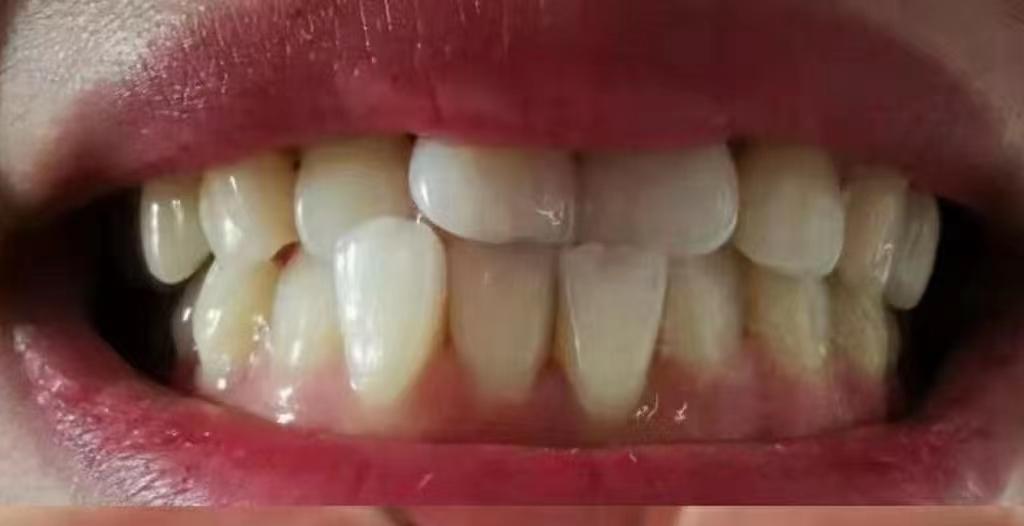

平時(shí)我們看到的自己牙齒可能這樣

看起來(lái)好像也還行

但你從牙醫(yī)視角看過(guò)自己的牙嗎!

就這兩顆自由飛翔的大門牙~能不影響咱的顏值嗎